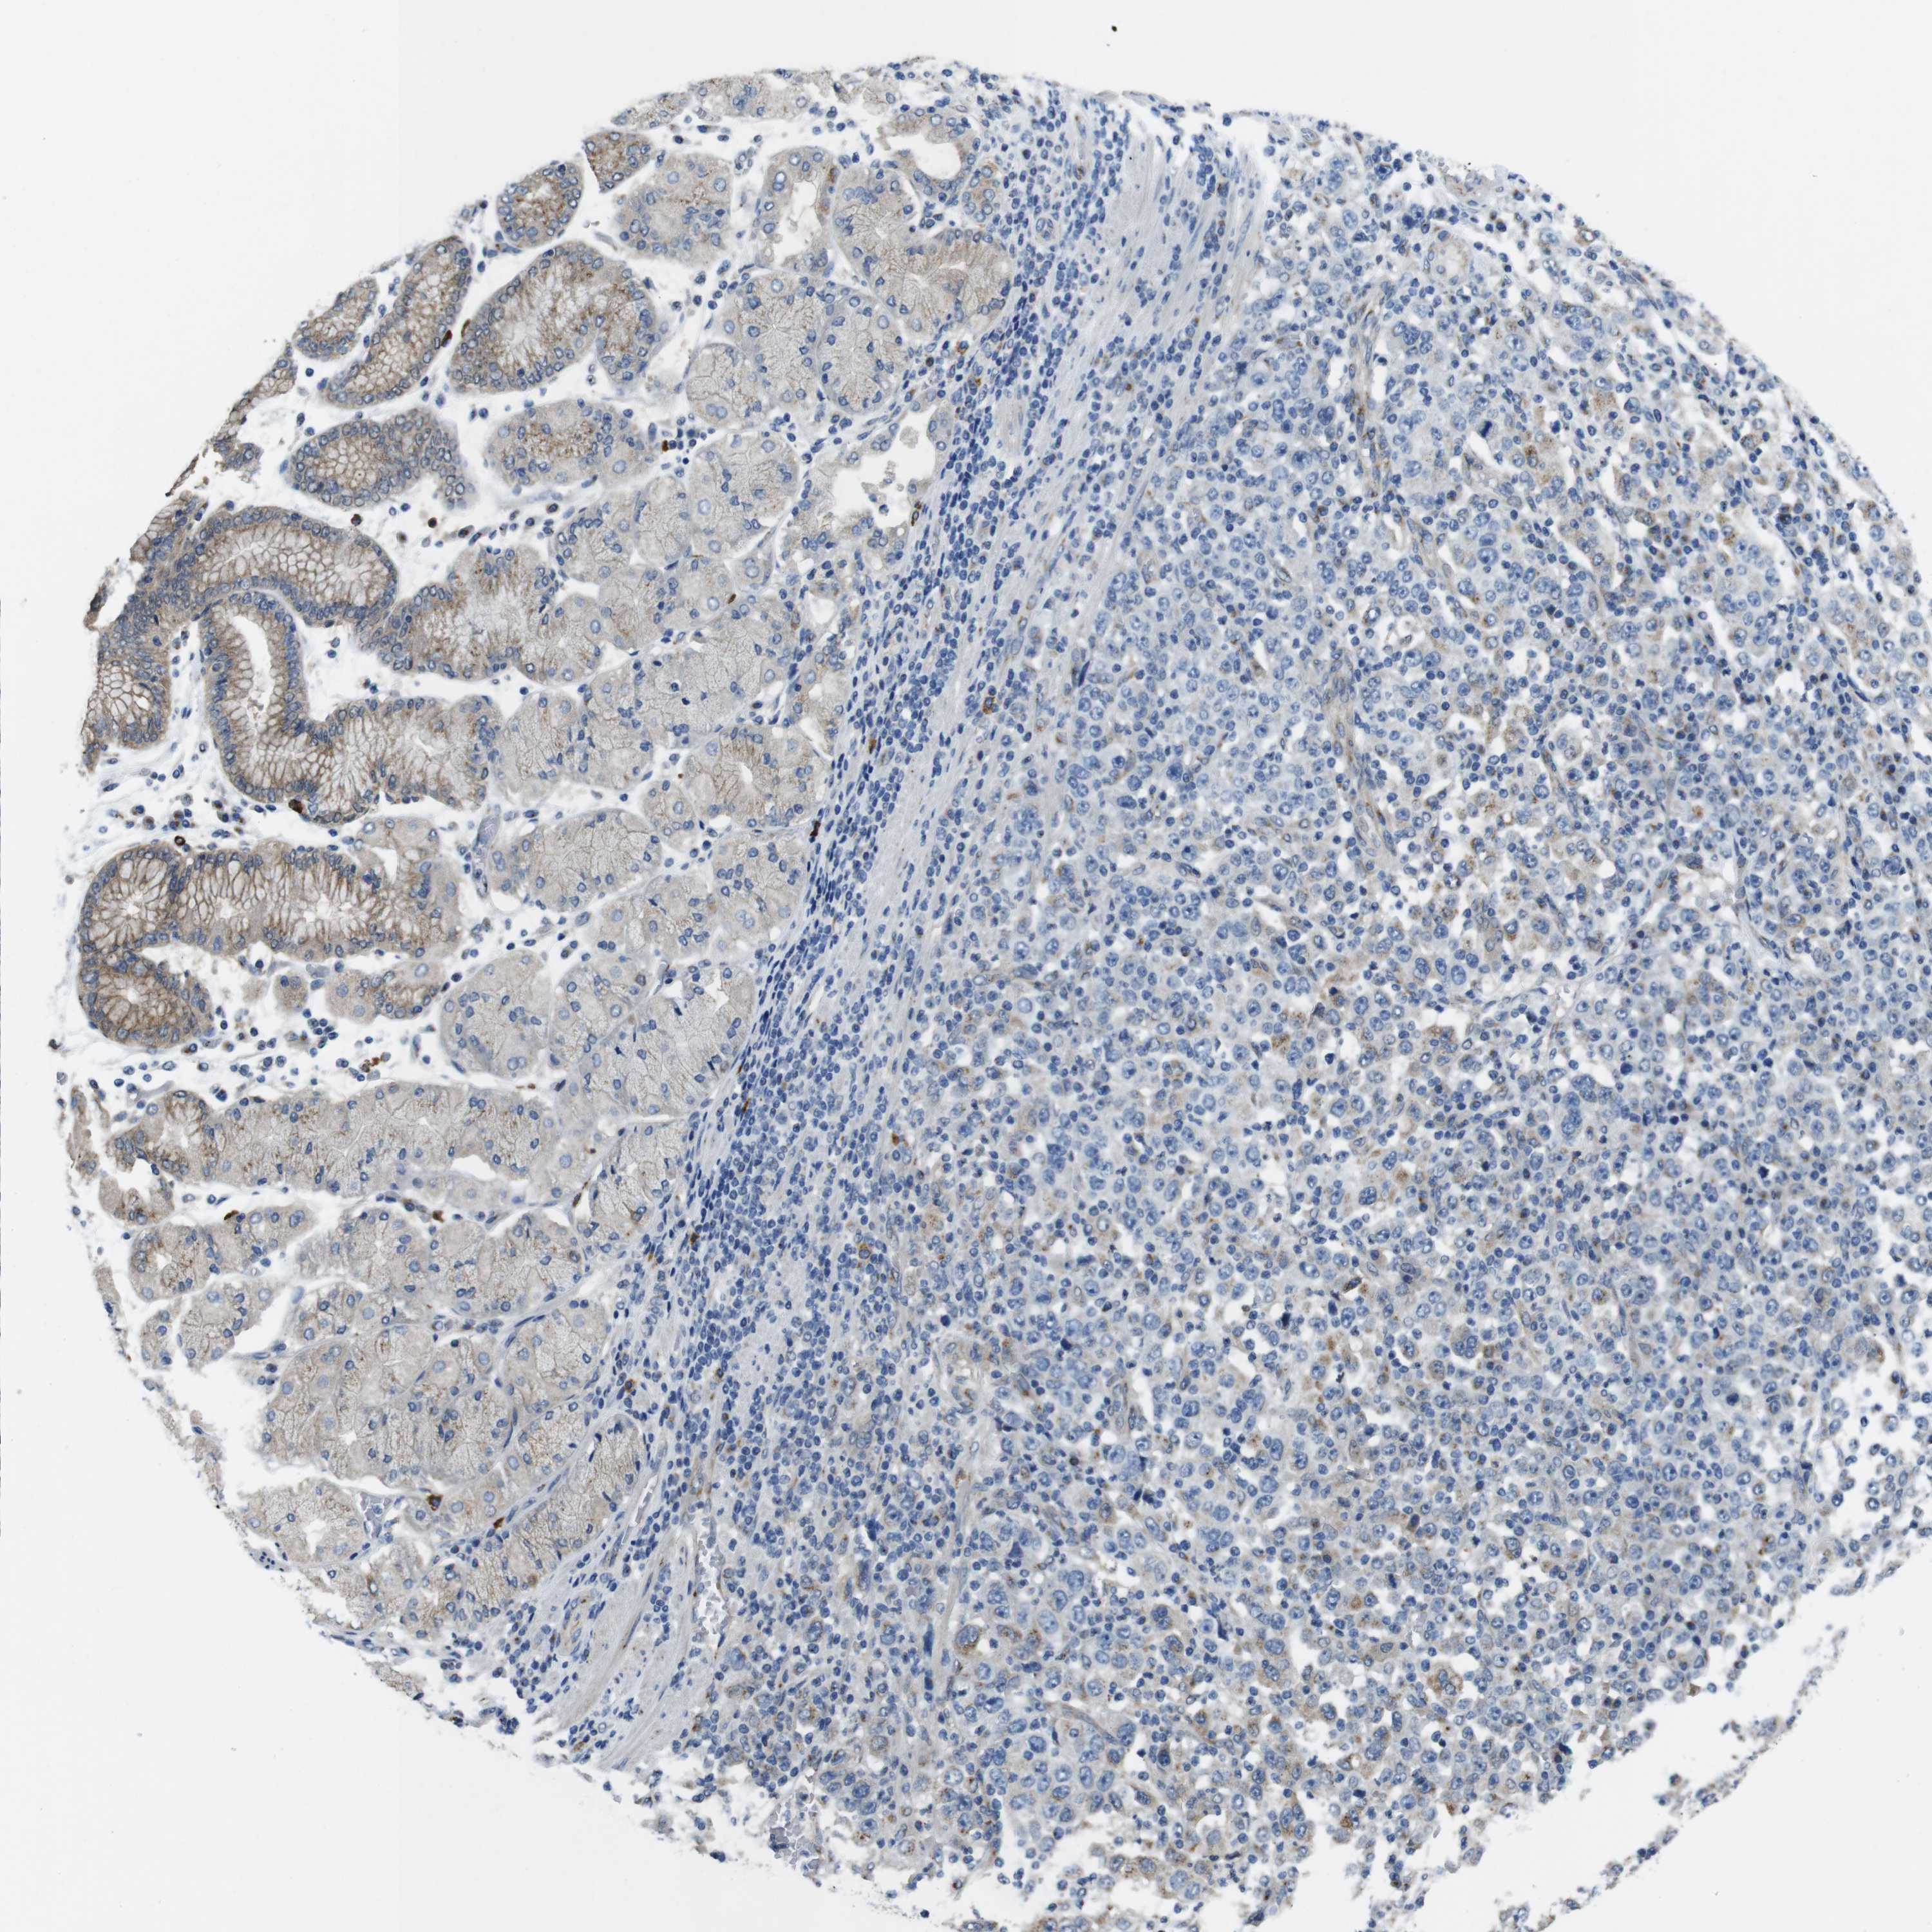

STOMACH CANCER - Protein expressioni

A mouse-over function shows sample information and annotation data. Click on an image to view it in a full screen mode. Samples can be filtered based on level of antibody staining by selecting one or several of the following categories: high, medium, low and not detected. The assay and annotation is described here.

Note that samples used for immunohistochemistry by the Human Protein Atlas do not correspond to samples in the TCGA dataset.

Antibody stainingi

Antibody staining in the annotated cell types in the current human tissue is reported as not detected, low, medium, or high, based on conventional immunohistochemistry profiling in selected tissues. This score is based on the combination of the staining intensity and fraction of stained cells.

Each image is clickable and will lead to virtual microscopy that enables deeper exploration of all samples and also displays staining intensity scores, fraction scores and subcellular localization as well as patient and tissue information for each sample.

Antibody HPA059131

Antibody CAB009936

Staining

High

Medium

Low

Not detected

Intensity

Strong

Moderate

Weak

Negative

Quantity

>75%

75%-25%

<25%

None

Location

Nuclear

Cytoplasmic/membranous

Cytoplasmic/membranous,nuclear

Adenocarcinoma, NOS

Adenocarcinoma, High grade